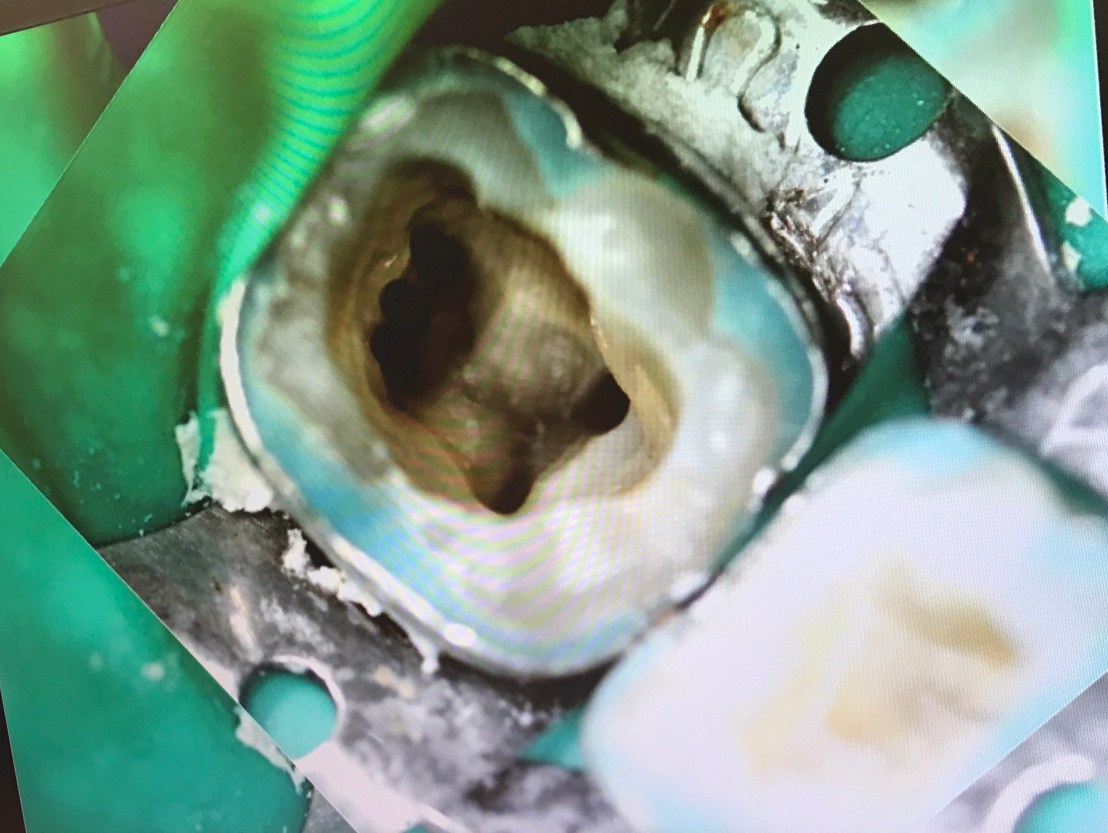

อีก case

จุดสีเหลือง คือ canal ที่ถูกต้อง

วงกลมสีแดง แสดงส่วนที่ถูก repair ด้วย MTA